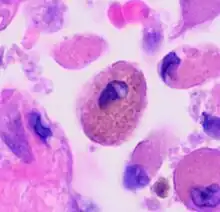

Comparison of pigmented pulmonary macrophages

| Disease | Macrophage name | Macrophage pigment appearance (HE stain) | Usual macrophage location | Associated medical history | Image | Image comment |

|---|---|---|---|---|---|---|

| Respiratory bronchiolitis | "Smoker’s macrophages" | Yellow to light brown and finely granular[4] | Airways (especially respiratory bronchioles) | Tobacco smoking | ![]() |

Smoker's macrophage in center |